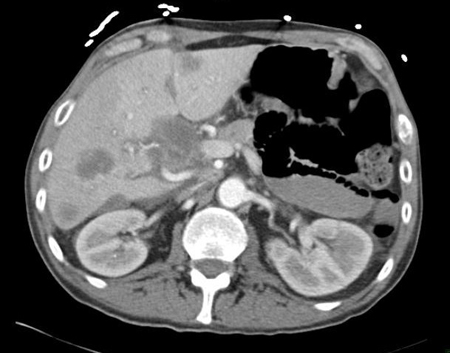

Adenocarcinoma of unknown primary site

CT abdomen with intravenous contrast, revealing numerous enhancing liver lesions in both hepatic lobes; percutaneous biopsy of a right lobe lesion revealed adenocarcinoma

From the personal collection of Dr D. Cosgrove